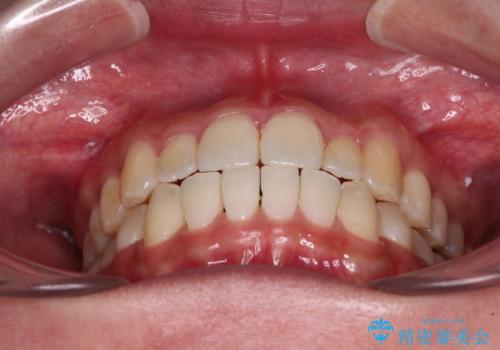

すきっ歯とオープンバイトをインビザラインで改善

- 前歯の上下スペースと前歯の隙間を気にして来院された患者様です。

インビザラインにより上下の前歯の隙間を閉じていくこととしました。

上下の隙間に舌が入り込むことが、すきっ歯やオープンバイトの原因であったため、舌の筋肉のトレーニングも並行して行い、後戻りの抑制を図りました。